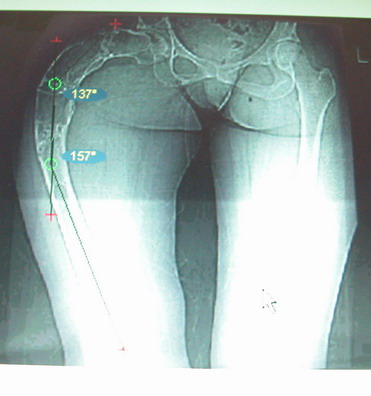

Моё мнение, что двойная остеотомия бедра с аппаратом Илизарова + Гексаподный механизм, или Тэйлора, В данной ситуации является методом выбора. Я очень извеняюсь за качество прилагаемых снимков, в которых я постарался отразить разницу междe одной и двумя остеотомиями бедра.

jo> отразить разницу межде одной и двумя остеотомиями бедра.